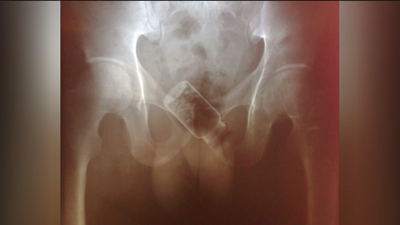

Las radiografías que muestran cómo se introduce la droga en las cárceles Las radiografías que muestran cómo se introduce la droga en las cárceles 05/03/2019

Así introducen los presos objetos en las cárceles madrileñas Así introducen los presos objetos en las cárceles madrileñas 05/03/2019